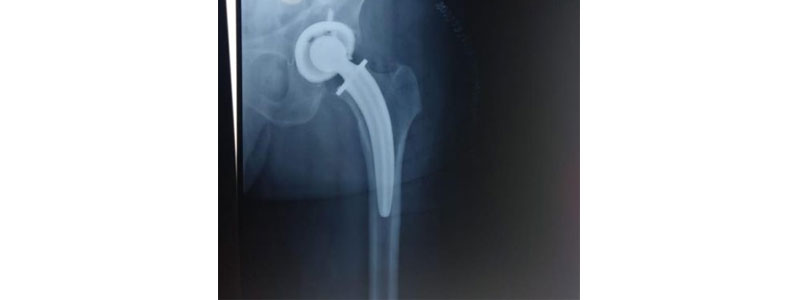

What is Hip Replacement Surgery(minimal invasive)?

During hip replacement, a surgeon removes the damaged sections of the hip joint and replaces them with parts usually constructed of metal, ceramic and very hard plastic. This artificial joint (prosthesis) helps reduce pain and improve function.

Also called total hip arthroplasty, hip replacement surgery might be an option if hip pain interferes with daily activities and nonsurgical treatments haven't helped or are no longer effective. Arthritis damage is the most common reason to need hip replacement.